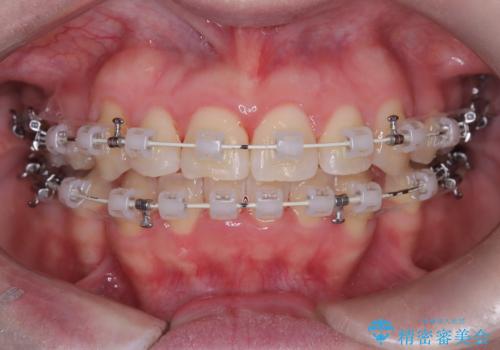

- 矯正装置

- 審美ワイヤー装置

- 患者様は、結婚式までに歯並びを整えたいとのご要望で来院されました。診断の結果、上下左右の第一小臼歯を抜歯し、歯列全体を整える計画としました。審美性を重視し、目立ちにくいホワイトワイヤーを使用した矯正を提案しました。治療期間は2年を目安とし、結婚式までに前歯の整列と噛み合わせを優先的に整えるスケジュールで進めました。定期的な調整と経過観察を通じて、計画的に治療を進めました。

結婚式までに仕上げるため、通常よりも細かく調整を行い、歯の動きを効率的に管理しました。審美ワイヤーを使用したことで、治療中も目立ちにくく、写真撮影などの日常生活での見た目の負担を軽減しました。抜歯部分のスペースを閉じる際には、前歯の位置や噛み合わせのバランスに配慮し、過度な力がかからないよう進めました。患者様の大切なイベントに間に合うよう治療計画を立て、理想的な仕上がりを実現しました。